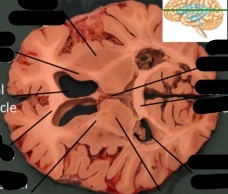

label, note important features

uncus is seen on the ventral (inferior) surface of cerebram, pointing towards the mamillary bodies or optic chiasm. following the uncus, the change in the basic organization of cortex indicates the hippocampus